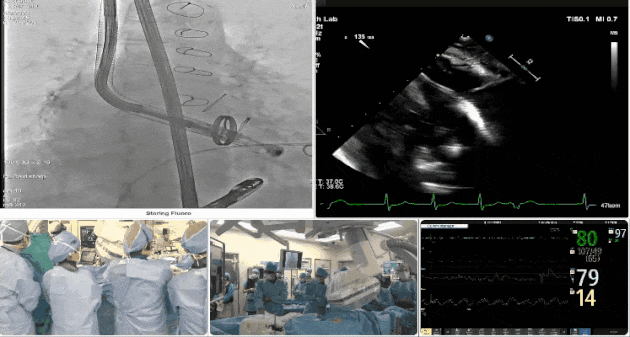

術(shù)中TEE觀察夾持件的位置

術(shù)后DSA

術(shù)后超聲評(píng)估瓣膜穩(wěn)定性良好,無(wú)瓣周漏

手術(shù)過(guò)程

術(shù)者采用經(jīng)右側(cè)頸靜脈入路的方式將輸送器送入患者心臟內(nèi),在TEE及DSA引導(dǎo)下調(diào)整輸送器頭端角度,使得輸送器與三尖瓣瓣環(huán)平面垂直。在輸送器進(jìn)入右心室后釋放室間隔錨定裝置,而后釋放瓣葉夾持件(2個(gè)耳片結(jié)構(gòu))成垂直狀態(tài)。在TEE及DSA確定夾持件固定至三尖瓣葉根部且位于右室側(cè)后釋放人工瓣心房側(cè)盤(pán)片。隨后調(diào)整瓣膜同軸性以及室間隔錨定件位置(貼合室間隔),前推藏針管并固定,進(jìn)而釋放室間隔錨定裝置,并再次確認(rèn)瓣膜位置、穩(wěn)定性及同軸性,合攏輸送鞘后撤出輸送器,最終順利完成LuX-Valve Plus人工三尖瓣瓣膜的植入。